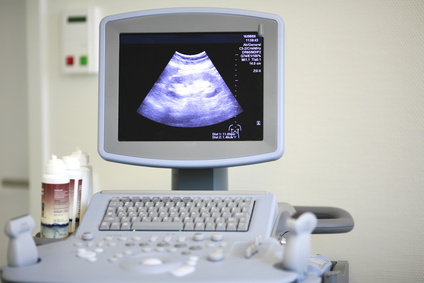

Die Ultraschall-Technik - auch Sonographie genannt - hat man sich

von den Fledermäusen abgeschaut. Mit Hilfe dieser Technik kann man gefahrlos viele innere Organe des Körpers untersuchen. Und das geht

so: Ein Schallkopf wird auf die Haut aufgesetzt. Dieser sendet

und empfängt Ultraschall-Impulse. Ein Computer berechnet daraus Bilder. Anhand dieser Bilder kann dann eine Diagnose gestellt werden.